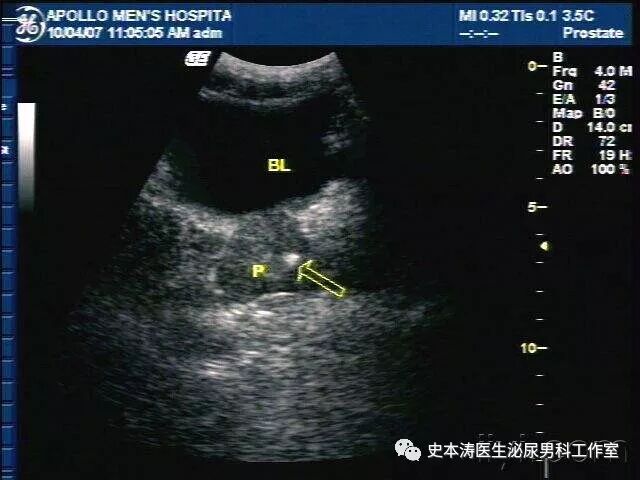

在影像学检查中,前列腺钙化表现为前列腺内强回声灶或高密度灶,随着超声技术的普及与提高,前列腺钙化的检出率显著增加。

典型的钙化和结石,都是表现为前列腺内单个或多个点状、斑点状、类圆形回声,半弧形强回声带,点状强回声多呈半弧形或条索状排列或相互融合成团,其后方可伴有声影或不伴声影。多分布前列腺内腺与外腺交界处。

应注意的是:需要与前列腺肿瘤钙化、结核钙化、膀胱结石、后尿道结石、精囊结石等相鉴别。